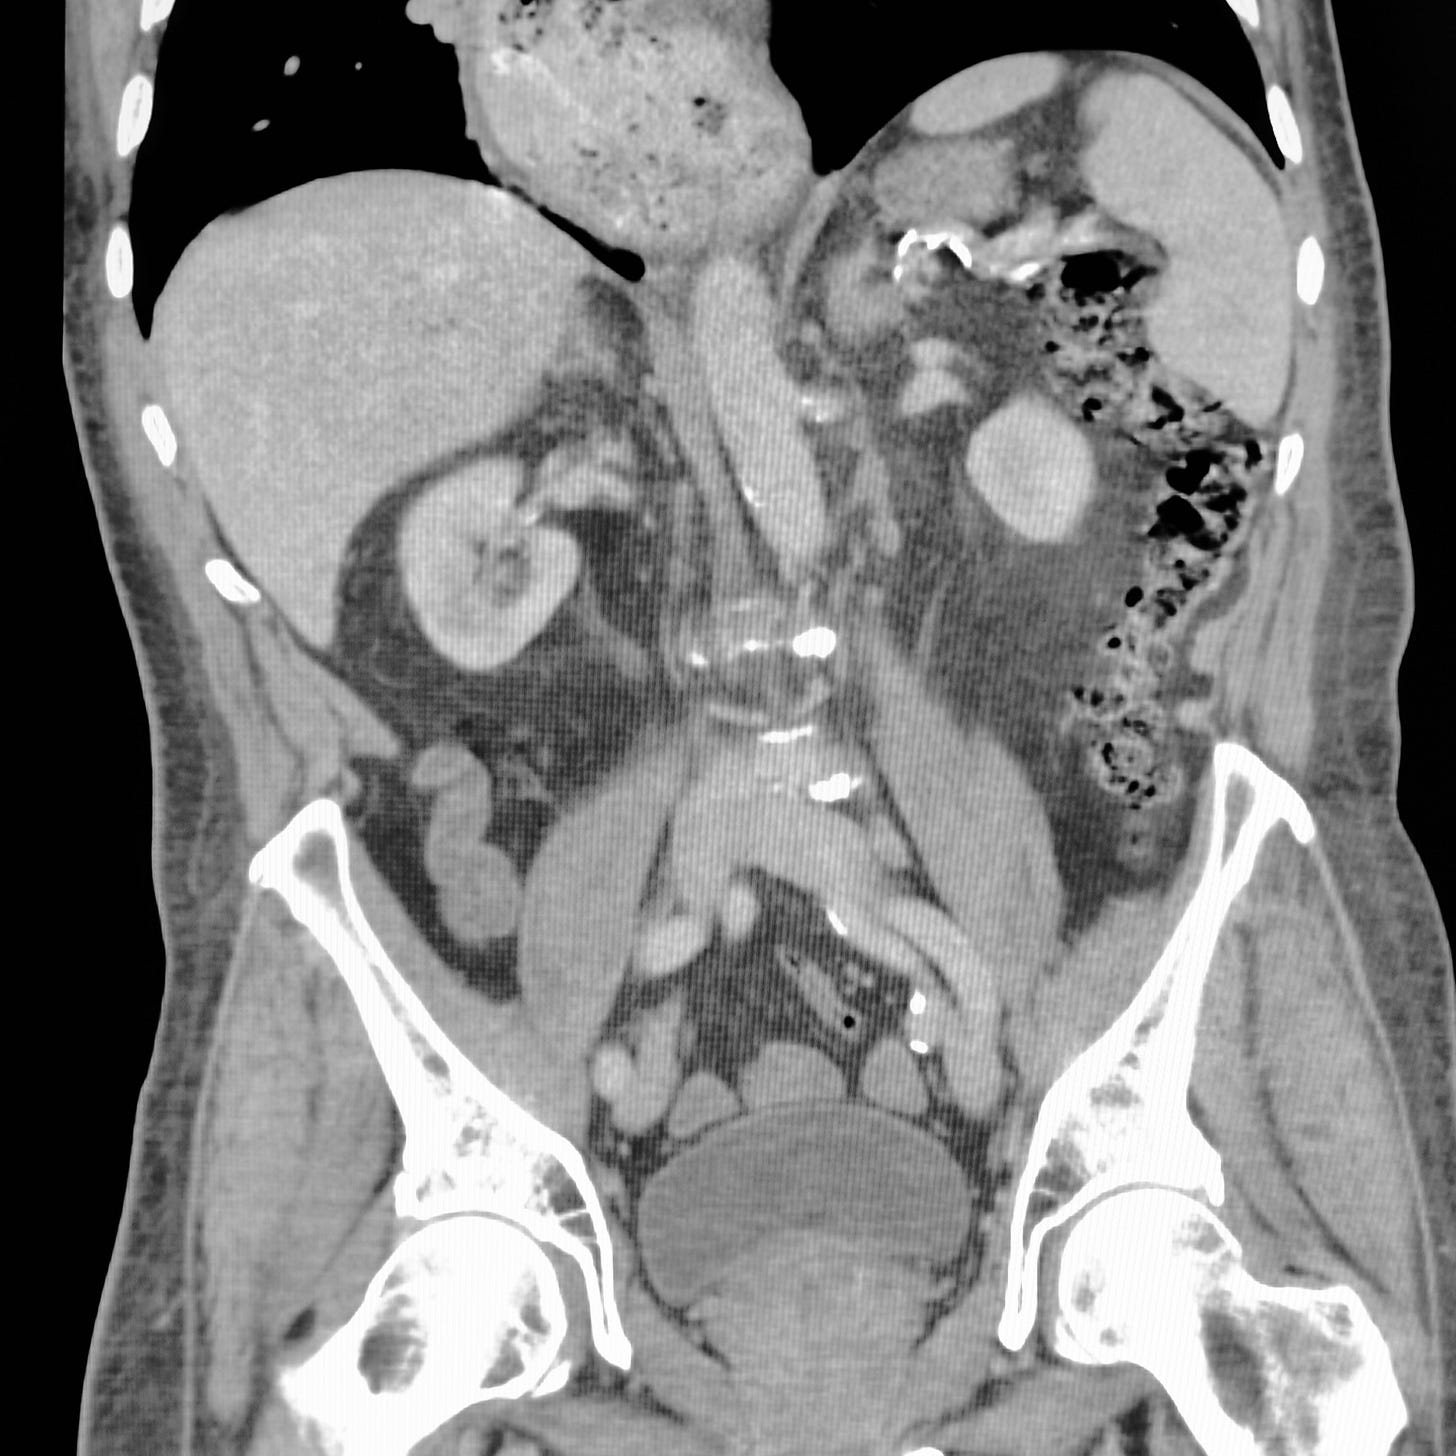

QuizNausea and vomiting for several monthsChestAlexander BaxterFeb 01, 2024ShareWhat is the diagnosis? What can cause this problem?Leave a commentClick here for diagnosis and discussionPreviousNext